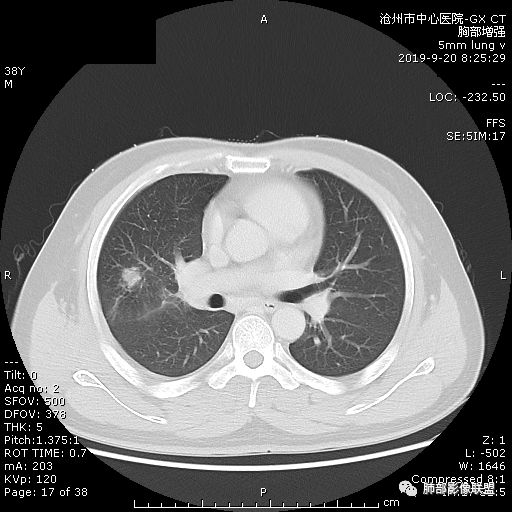

年轻男性,咳嗽2月,痰中带血,胸痛,炎症指标稍高,肿标正常。影像,右肺上叶不规则团块影,浅分叶,伴边界不清磨玻璃影,从外周向内分布,局部胸膜增厚,病灶中央坏死,坏死边界尚清,空洞形成,空洞内壁光滑;考虑炎性肉芽肿性病变,结核可能,鉴别恶性肿瘤及真菌感染。病灶分布特点不考虑隐球。

右肺上叶不规则病灶,密度不均,有分叶,边缘不清,中央有坏死,坏死壁尚光滑,增强壁有强化,病灶有外朝内,整体收缩为主,慢性病程,考虑炎性病变,肺脓肿或者结核,淋巴结肿大,支气管截断,胸膜脂肪间隙变窄,加个鉴别恶性肿瘤。

右肺上叶分叶状肿块(冠状位尤为明显),内见液化坏死,支气管截断,收缩力强,周围有片状影,右侧腋窝及纵隔淋巴结增大,增强有强化,定性恶性病变,脓肿形态及临床症状不符,暂排除。

38岁,男性,慢性咳嗽2月,右胸痛8天,无发热;白细胞高,肿瘤标志物不高;右上肺不规则块状影,周围有磨玻璃影,边界清,整体有膨胀感,分叶,与胸膜糊墙,并见栽赃,增强肿块中央坏死,周边强化。综合考虑,考虑恶性,鳞癌可能。

38岁,男性,慢性咳嗽2月,右胸痛8天,无发热。白细胞高,肿瘤标志物不高。右上肺不规则块状影,周围有磨玻璃影,边界模糊,整体有膨胀感,分叶,与胸膜糊墙,可疑栽赃,增强肿块中央坏死,边界清,周边强化明显,强化区有低密度影,壁不规则,跨叶生长,支气管截断,伴支气管扩张,综合考虑腺癌

中年男性,咳嗽2月,伴胸痛8天,少许痰血,无发热中性粒明显增高,低氧,肿标不高,右肺上叶不规则实性肿块,深分叶,局部凹陷呈月牙铲改变,多坏死,多空泡,前段支气管分支似见堵塞,2R、4R、10R和7区淋巴结肿大。考虑肺癌可能,建议支气管镜活检

晨读:右肺上叶不规则团块,深分叶,膨胀为主,有部分收缩,叶间裂牵拉上移,内多液化坏死,有支气管扩张,右肺上叶大支气管近端通畅,远端堵塞,说明肿块来源于外周,纵隔及右肺门淋巴结肿大,胸膜糊墙为主,年轻人,肿标不高,炎性指标高,综合考虑炎性肉芽肿放前面脓肿,结核,肿瘤放后面。

1.肺脓肿是有化脓菌引起的肺部化脓性炎症,病变变化、坏死及坏死物排出后形成空洞为其主要特征,可为病原菌经呼吸道感染或经通过血行感染。

2.根据临床经过分为急性和慢性。急性肺

脓肿变现为发热 、咳嗽、胸痛、咳血。白细胞总数增加。慢性肺脓肿可由急性肺脓肿发展而来,也可无急性过程,白细胞总数无可变化。

3.ct表现:肺脓肿可呈结节状或团块状,有时呈不规则形,气道来源肺脓肿常单发,血行来源常多发,边缘模糊,部分病灶周围可见片状肺实变及磨玻璃影;病灶中央为液化坏死区,若脓肿与支气管相通,脓液排出可形成空洞,空洞内可形成液平;急性肺脓肿内壁多不规则;慢性肺脓肿洞壁较厚,一般不规则或形成多房空洞:CT增强扫描空洞壁可见强化,空洞壁为纤维肉芽组织,呈典型的环形强化;慢性肺脓肿周围可有较广泛的纤维索条影,可伴支气管扩张.肺

气肿或胸膜增厚表现。

今天病例坏死周围也可以看到明显强化的脓肿壁,只是局部脓肿壁不规则模糊,部分脓肿壁规则清楚。